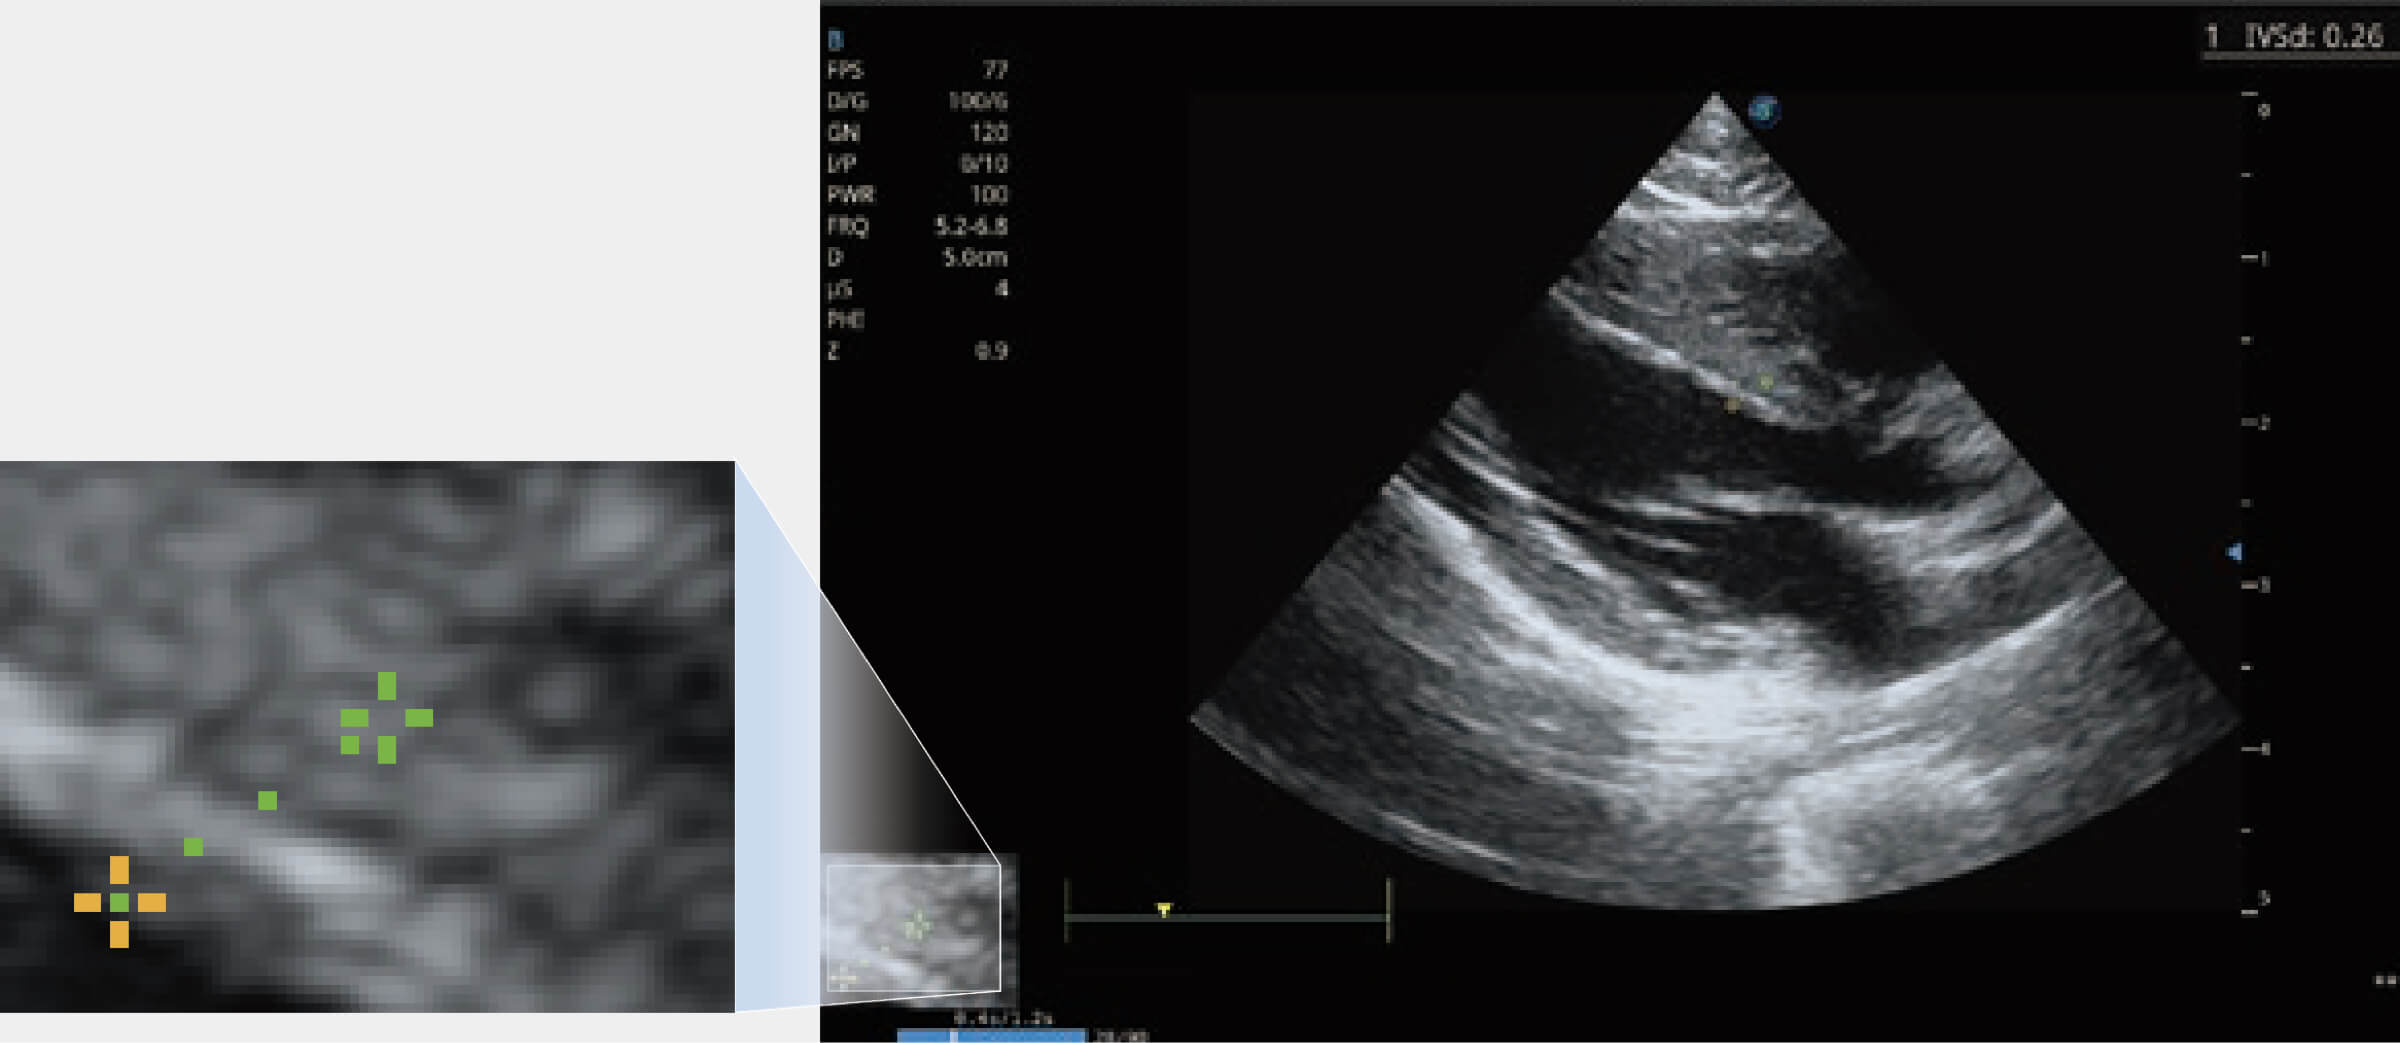

能夠基于左心室壁追蹤和辛普森法,自動(dòng)計(jì)算射血分?jǐn)?shù),支持多個(gè)可移動(dòng)點(diǎn)描跡,與手動(dòng)測(cè)量相比,極大節(jié)省了動(dòng)物醫(yī)生的時(shí)間和精力。

通過360度任意調(diào)節(jié)3條M型取樣線,在同一心動(dòng)周期上觀察心臟不同位置的運(yùn)動(dòng)曲線,得到準(zhǔn)確的心功能測(cè)量數(shù)據(jù),有效評(píng)估心肌運(yùn)動(dòng)及左心室功能。

當(dāng)心臟測(cè)量結(jié)果超出正常范圍時(shí),可實(shí)時(shí)預(yù)警提示動(dòng)物醫(yī)生,減少疾病漏診概率。